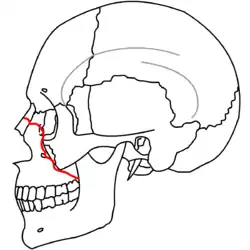

Traditionally, Le Fort described three types of fractures. All three fractures involve the nasal septum and the pterygoid plates.[2]

- The Le Fort I fracture (horizontal maxillary fracture) consists of a horizontal fracture through the pterygoid plates and maxillary bone between the hard palate and the orbits.[5] Involvement of the nasal aperture differentiates this fracture from the other two Le Forts.[5] Historically, this fracture was eponymically known as a Guérin fracture.[3]

- The Le Fort II fracture (pyramidal fracture) includes a fracture line from one of the lateral vertical buttresses across the maxillary bone, extending into the inferior orbital rim and crossing the midline (either through the nasal root or nasal bones).[5] The defining feature of this fracture pattern is involvement of the inferior orbital rim.[5] When viewed from the front, this fracture is classically shaped like a pyramid.